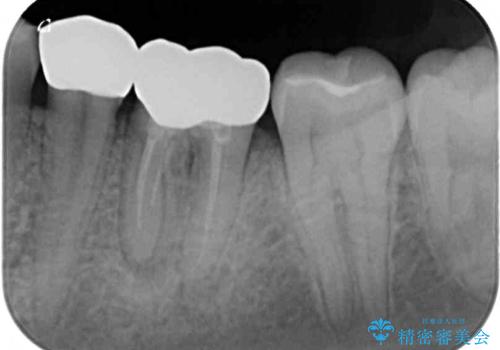

むし歯がとても大きく、歯茎に歯の一部が埋もれてしまっているため、汚れが溜まりやすくなっている状態でした。

根歯の挺出(歯を引っ張り出す部分矯正)、歯周外科処置などを行った後、オールセラミッククラウンにて補綴することとしました。